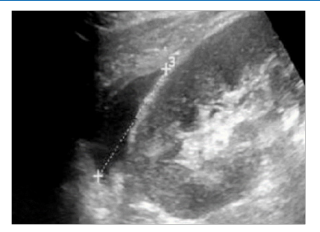

Figure 4: Reduced Corticomedullary Differentiation in a 13-Year Transplantation Duration of a 40-Year-Old Male

Ultrasonographic morphologic parameters are commonly utilized to evaluate the current graft function and the characteristics that predict rejection and pathological processes. These metrics have been used to correlate with pathological alterations involving the transplant and rejection. This cross-sectional descriptive study aimed to evaluate the transplanted kidney using ultrasonography in Ahmed Gasim Specialized Hospital of Cardiac Surgery and Renal Transplantation, Khartoum state, from September 2022 to January 2023. The demographic results of this study revealed that renal transplantation is more common in males than females (70% vs. 30%). This is primarily due to the high prevalence of chronic renal disease among hemodialysis patients, a key factor influencing the gender distribution in renal transplantation. Nonetheless, this result is in line with another study that found that men made up 68.5% of hemodialyzed patients in need of renal transplantation (RT) ; another study revealed that renal transplantation is more common in males than females (77.4% vs. 22.6%) [9,10]. This consistency across studies, including ours, provides a robust and reliable understanding of the gender distribution in renal transplantation, instilling confidence in the robustness and reliability of our findings. The patients, most commonly aged between 18 and 60, with a mean age of 40.85, were found to be significantly affected by ESKD. These findings align with previous studies, such as the one on the incidence of ESKD with RT in Sudanese populations and the work of Moawia Gameraddin in 2017 [10,11]. The study found that the highest frequency of transplantation duration was (1-5) years in 30 patients (50%); this is not compared with any previous studies because they didn’t mention it. In the current study, a sonographic assessment of the renal cortex of the transplanted kidneys showed reduced corticomedullary differentiation found in 3 patients (5%), which agrees with Abd Elmotaal 2019 [12]. The study found the renal artery was normal in all patients (100%), which disagrees with Irshad A. in 2008, who found that the most common type of complication of renal transplant was renal artery stenosis (14%) [13]. Renal calculi were found in 1 patient (1.67%), and this disagrees with Wanasi Myson 2007, who reported calculi as (0%) and Abeer El-Motaal in 2019 [12], who reported calculi in (10%) [14]. The study concluded that the incidence of transplantation was higher in males. The highest frequency of transplantation duration was found (1-5) years; the volume of transplanted kidneys was found to increase by 15% about long transplantation duration. The most common type of complication of renal transplantation was perinephric fluid collection.